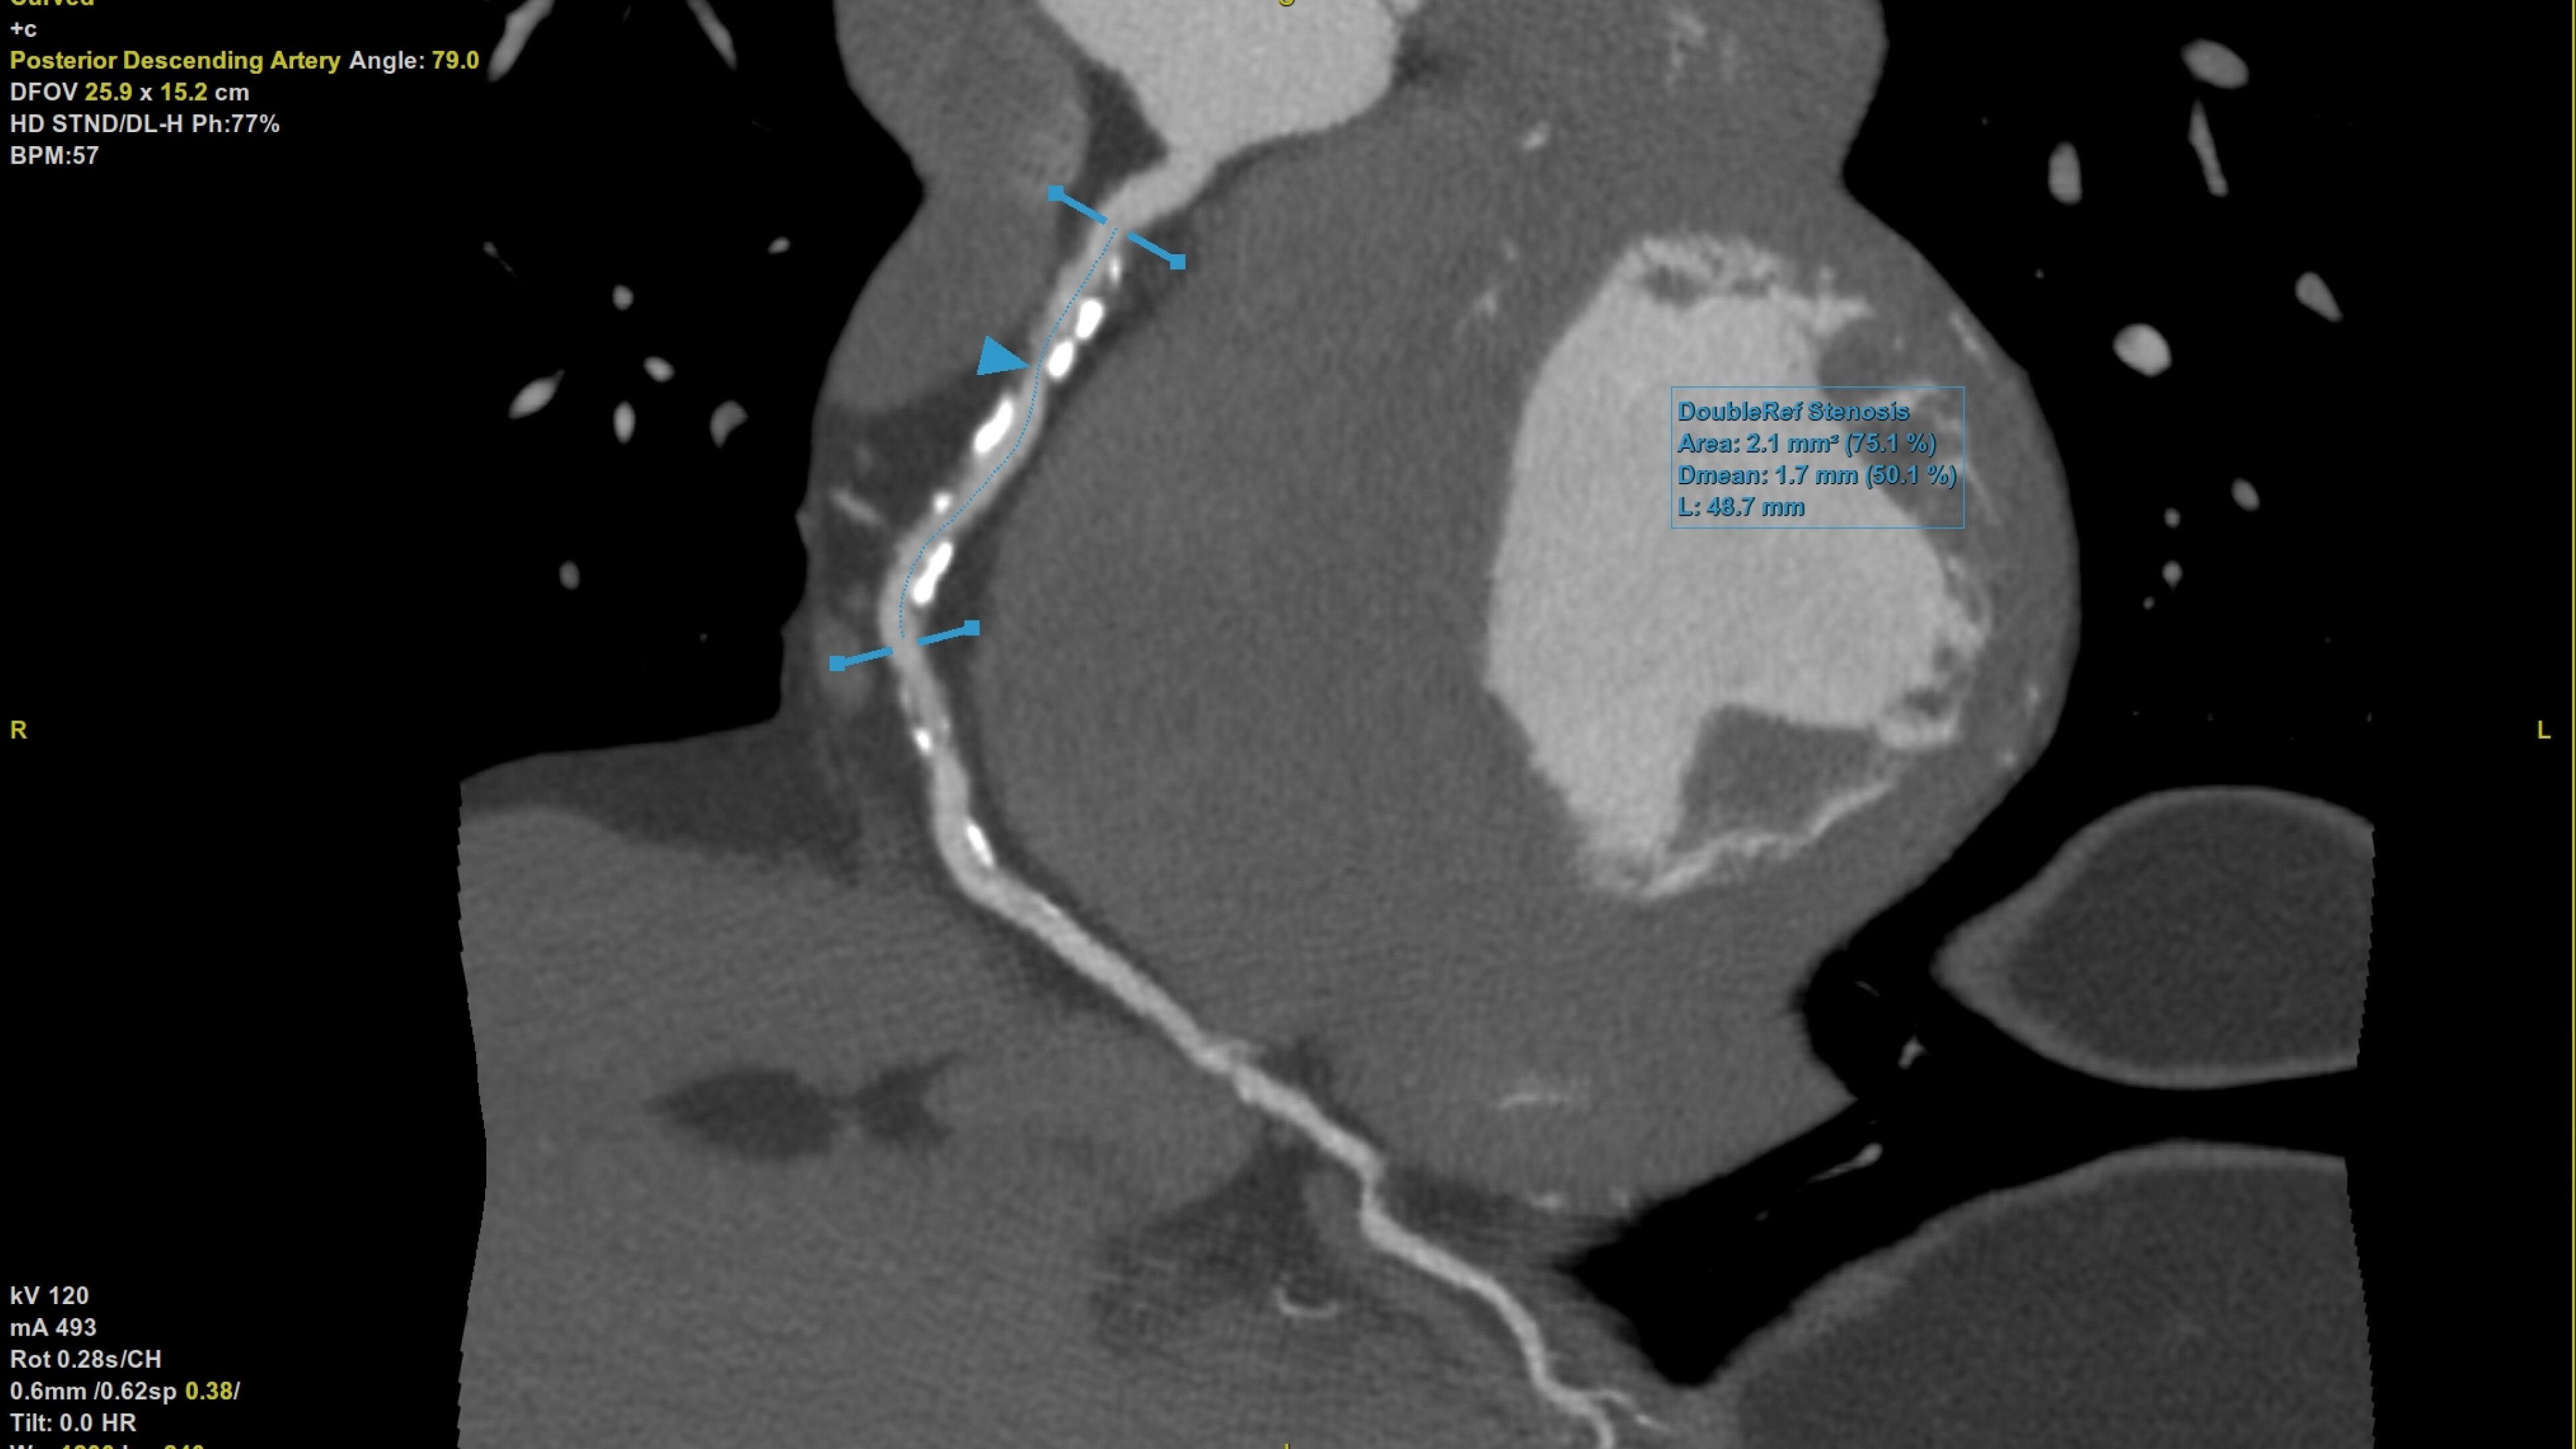

• Plaque ID provides volume measurements for four distinct Hounsfield ranges to aid with identification and visualization of coronary plaque

Plaque ID tool assists in visualizing and quantifying plaque burden